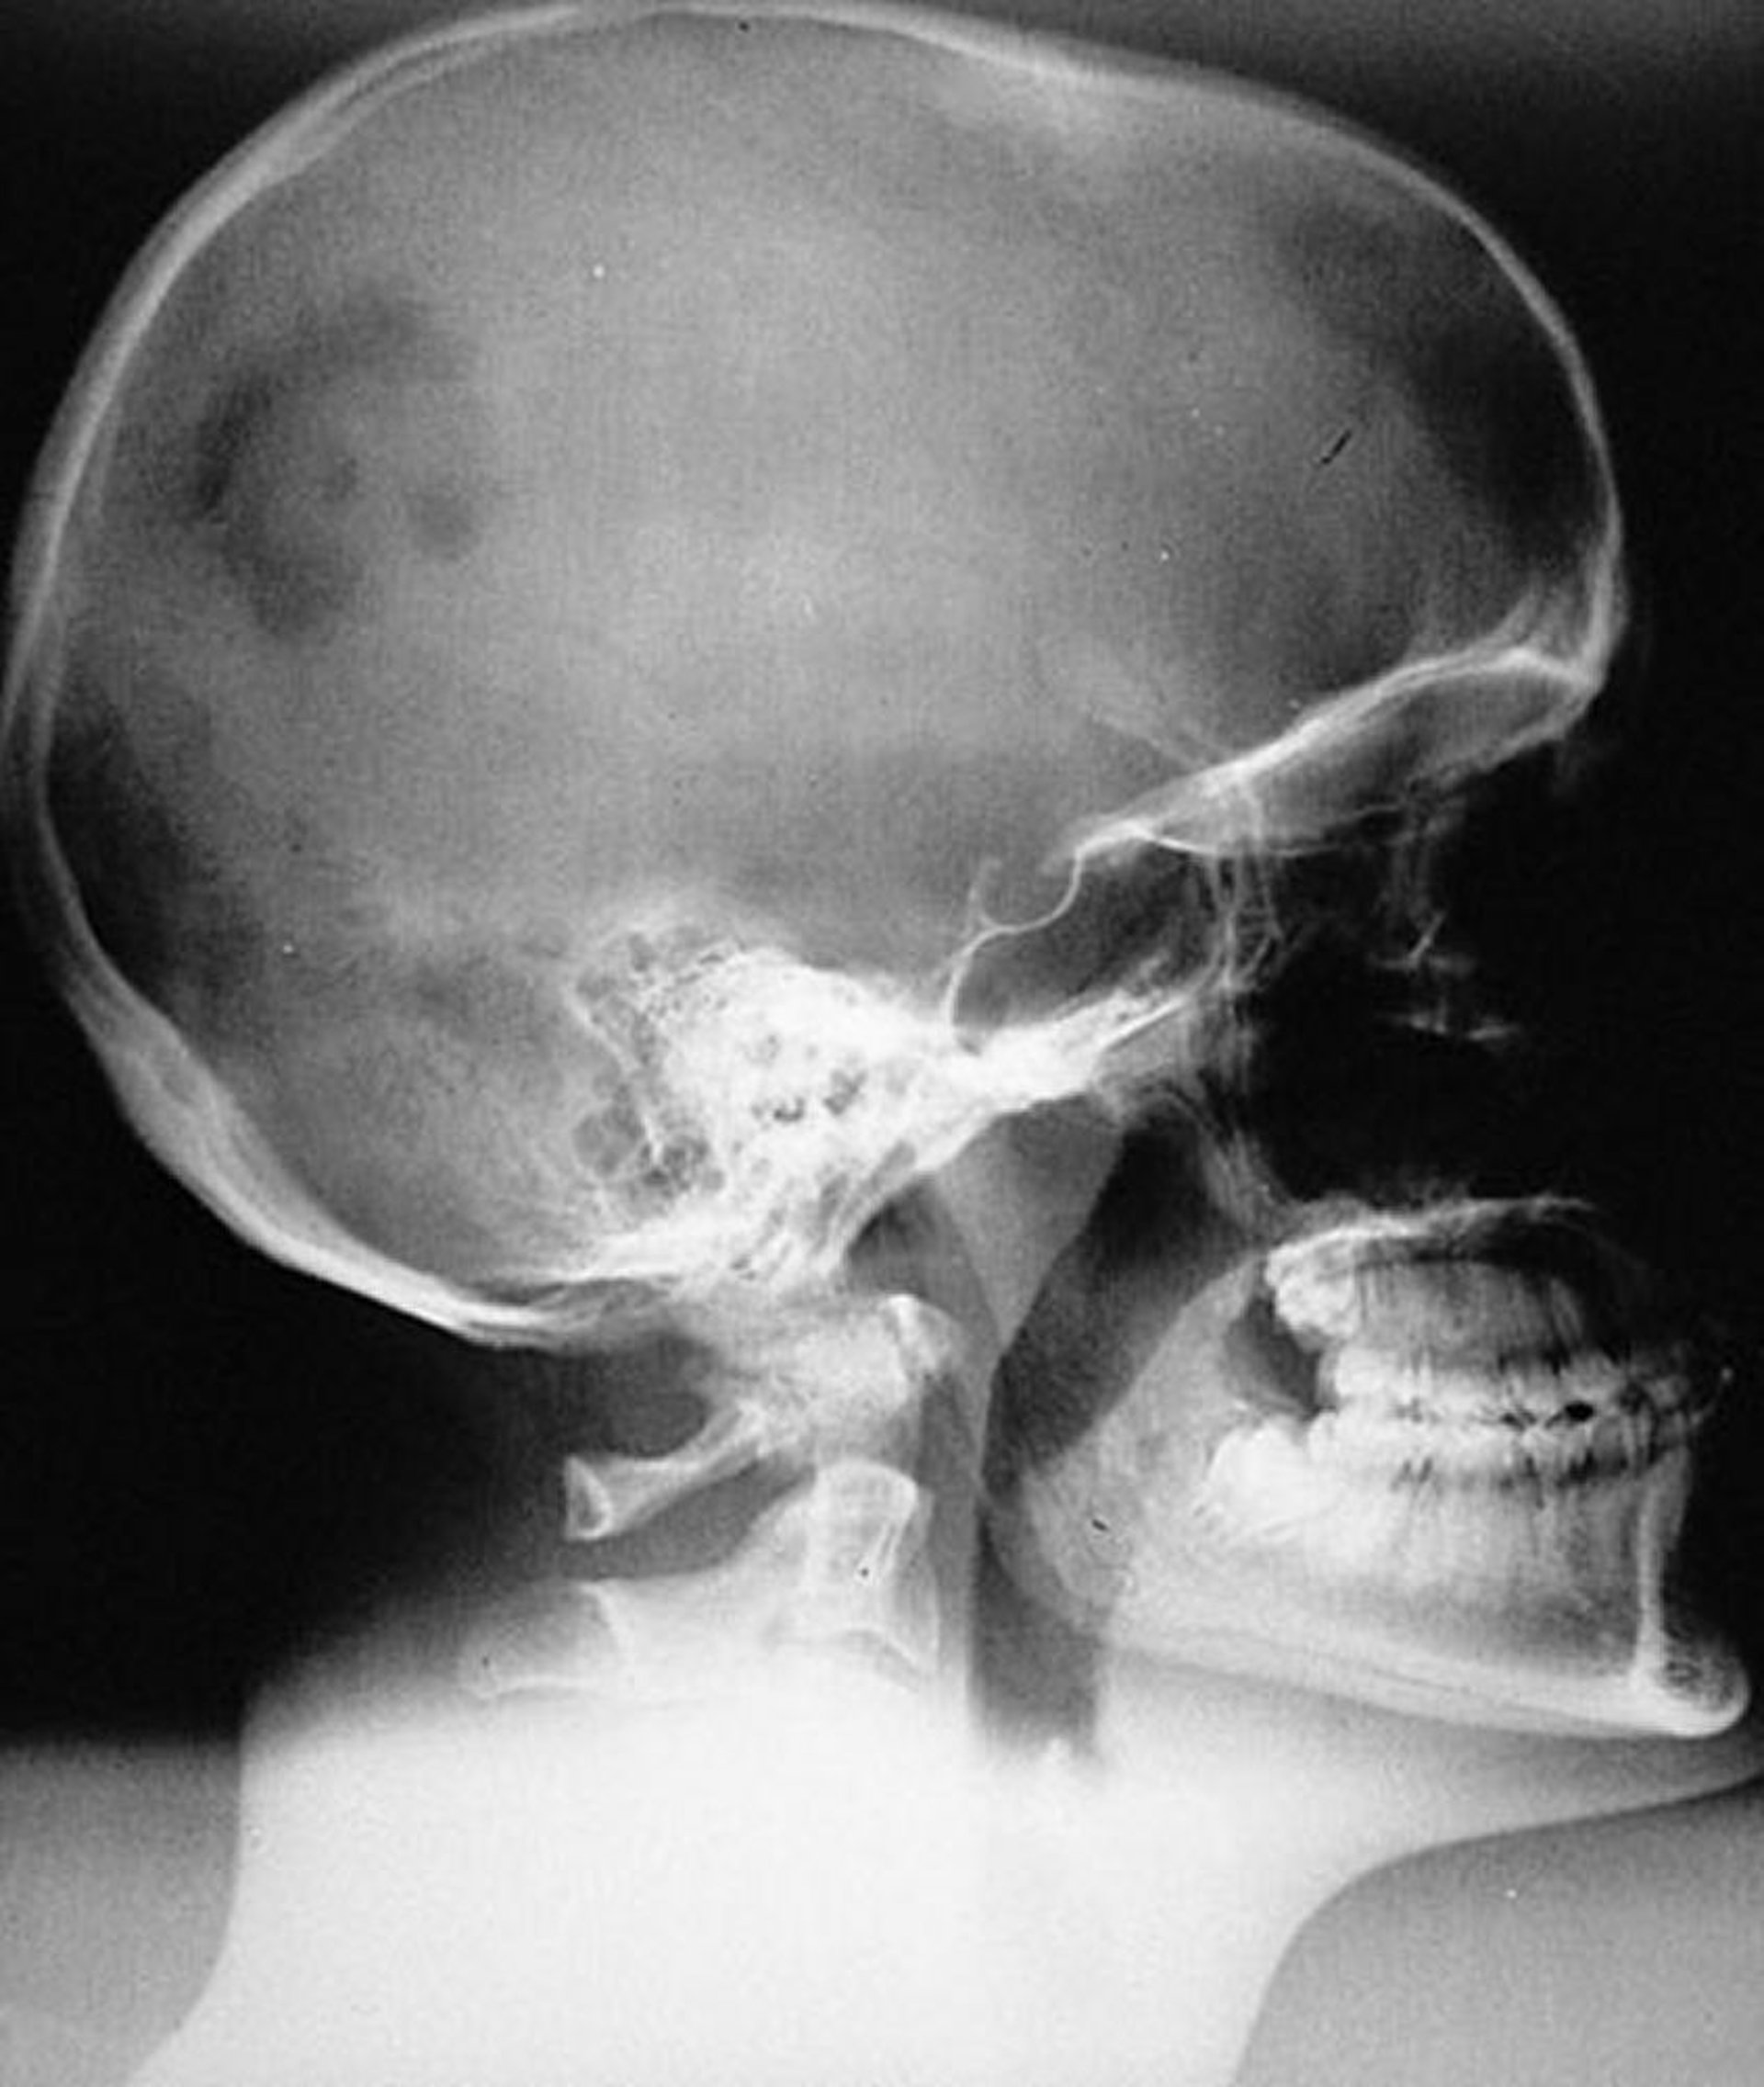

Langerhans-Zell-Histiozytose (eosinophiles Granulom) des Schädels

Röntgenbild einer typischen monostotischen unifokalen LCH-Läsion (eosinophiles Granulom) am Schädel. Die Läsion ist scharf begrenzt, aber nicht abgeschrägt.

By permission of the publisher. From Swearingen B, Schaefer P, Primavera J, Klibanski A. In Atlas of Clinical Endocrinology: Neuroendocrinology and Pituitary Disease. Edited by S Korenman (series editor) and ME Molitch. Philadelphia, Current Medicine, 2000.